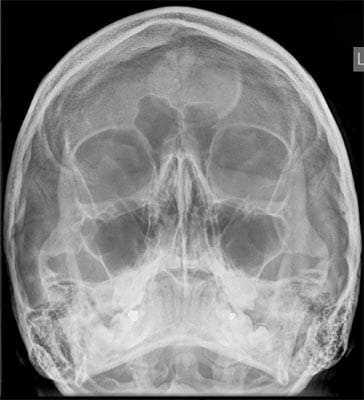

Artefact sensitivity within digital radiography: examples from a major trauma centre

Since the introduction of the new systems several issues in relation to image artefacts have surfaced. Three different examples will be put forward in this article in order to show some problems that have been encountered and to provide a learning experience for other trusts and institutions moving over to the ever-increasing new era of digital radiography.